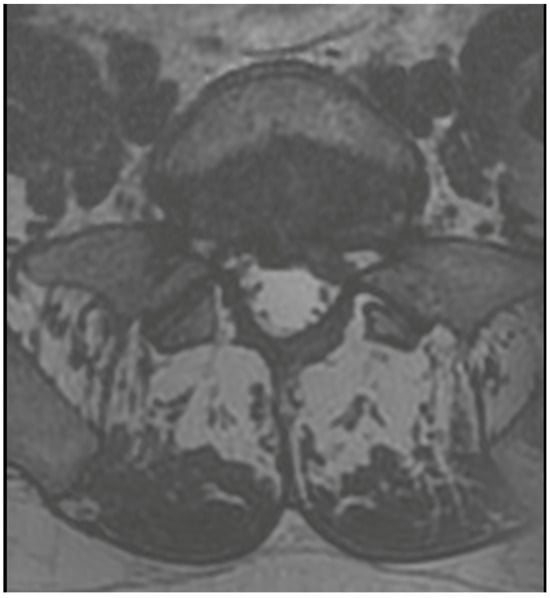

3.4. Case 1: Transient Cauda Equina Syndrome Due to Subdural Hematoma